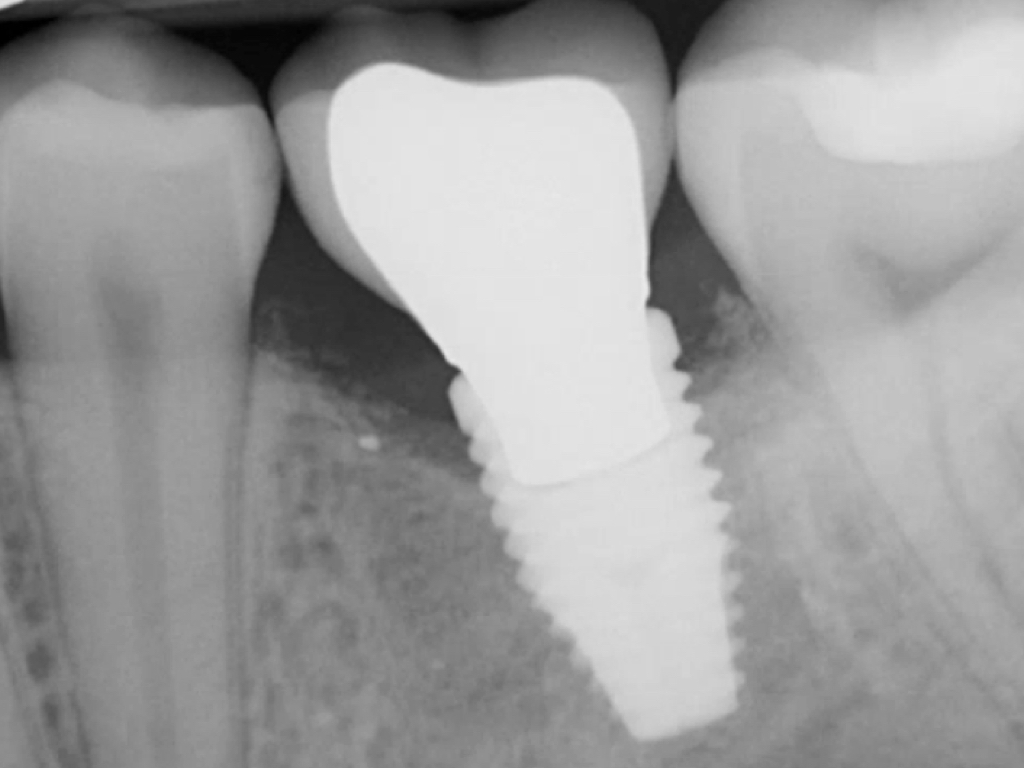

Fig 6. Periapical radiograph indicates proximal bone loss only.

Probing is useful to determine the presence of biological complications at the buccal and lingual sites of implants, which cannot be evaluated on a radiograph (Figure 6 through Figure 8). Because of the absence of a periodontal ligament, bone loss on the buccal and lingual aspects of an implant indicates loss of support for the implant and may be a sign of additional circumferential bone loss around the implant.35